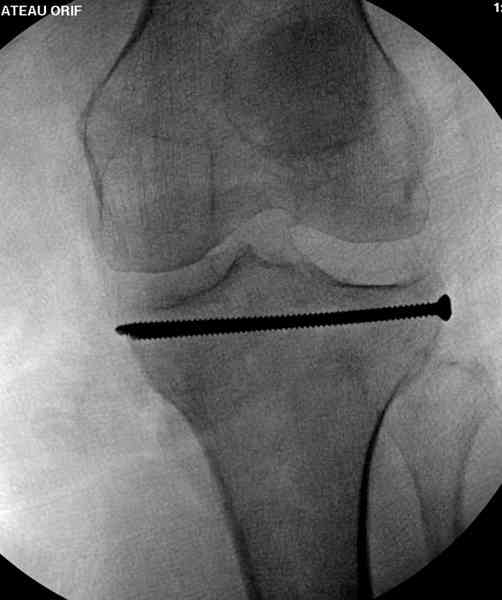

Это техника применяется, когда имеется

центральная импрессия, а при ипрессии с краевым переломом - после приподнимания импрессии опорная (Butress) пластина, как на снимке.